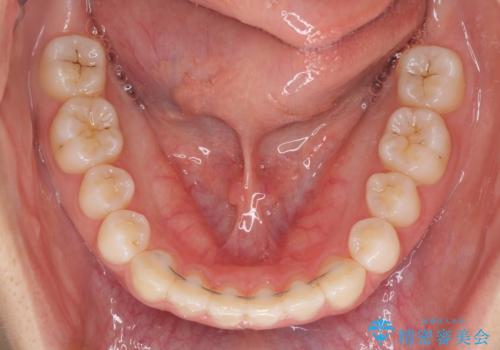

海外勤務中でも矯正治療 インビザラインによる軽度叢生改善

- 前歯のデコボコを気にして来院された患者様です。

治療期間中に海外勤務になる可能性が高いことが分かっていましたが、矯正治療を始めたいとのことでしたので、インビザラインを用いて治療することとしました。

通常であれば半年から10ヶ月程度で終了する歯並びでしたが、海外に長期出張することになったため、1年10ヶ月の期間を要しました。

出張に行かれてしまうと追加のマウスピースを発注できないため、マウスピースの交換頻度を低くし、一時帰国のタイミングに合わせていくことで、スムーズに進めて行くことができました。